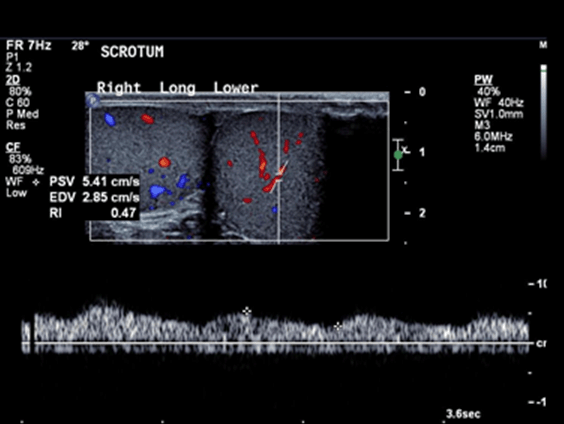

Ultrasound of the scrotum showed polyorchidism with two distinct testes within each hemi-scrotum. The upper left testis measured 3.4x2.5 cm with no Doppler flow to the testis and adjacent hyperemia in the epididymis (Figure 1). The lower left testis measured 1.7x3.3 cm with decreased Doppler flow (Figure 2). The right hemi-scrotum contained two distinct testes measured 2.3x2.6 cm in the right upper testis (Figure 3) and 3.5x3.3 cm in the right lower testis (Figure 4).

Figure 2: Left lower testis measured 1.7x3.3 cm and decreased Doppler flow to the testis.

The main finding is the presence of a mass with identical echotexture to the ipsilateral testis with the similar flow characteristics to the ipsilateral testis on the color Doppler sonography [5]. In our case, the flow to the left supernumerary testis was absent and the flow to the left ipsilateral testis was also decreased which raised the suspicion of left sided supernumerary testicular torsion.